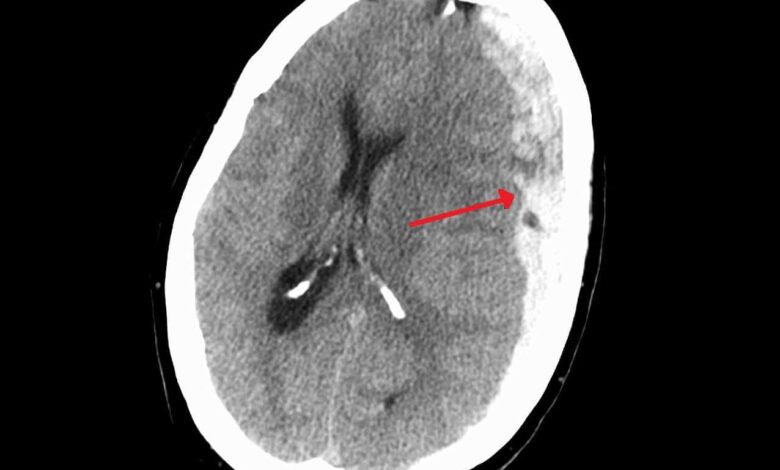

In a situation where treatment outcomes are difficult to predict, specialists from Perm (Wagner Perm State Medical University and PNIPU) set out to identify objective criteria for assessing patients’ prognoses. They analyzed medical records of individuals admitted to the hospital within six hours of injury and divided them into groups based on hematoma location: frontotemporal, parietotemporal, and frontoparietooccipital regions.

The results showed that the location of the hemorrhage directly affects the chances of recovery. The most favorable outcomes were observed in patients with frontal-temporal hematomas—this group was the most likely to regain independent living. In contrast, when the frontal-parietal-occipital area was affected, the prognosis worsened significantly: these patients arrived in a more severe condition, and the hematoma volume was greater.